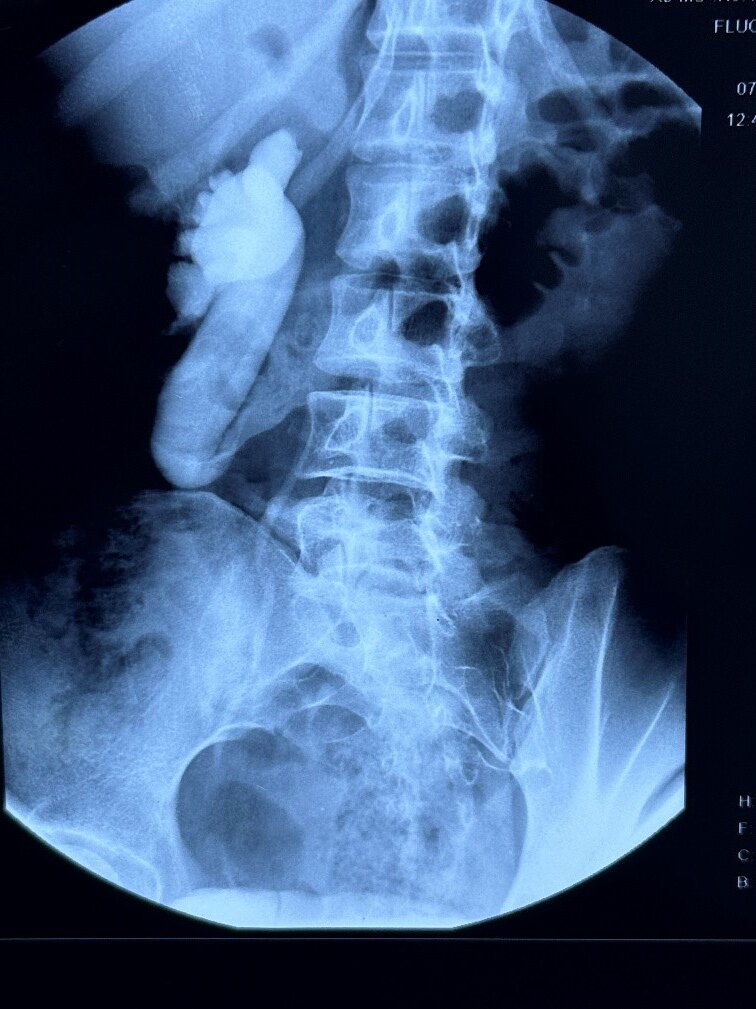

患者信息:女性,24岁,以“右腰腹部疼痛1年”入院。患者1年前无明显诱因出现右侧腰腹部疼痛,性质不剧烈,可忍受,无血尿和尿急,尿频,尿痛,CT和IVP显示右肾积水,考虑腔静脉后输尿管,在当地医院给予留置输尿管支架治疗,半年前拔除支架后,肾积水复发,为求进一步诊治来我院。IVP及数字三维重建如下图:

IVP结果

1-6.jpg